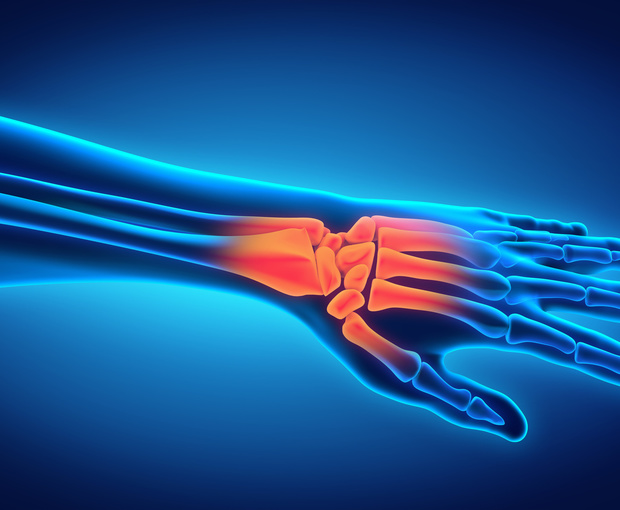

A wrist fracture has the potential to impact daily life for an extended period of time. Wrist fractures can result from falls, sports activities and improper lifting, among other things. Owing to the complex architecture of the bones, muscles and ligaments in the wrist and hand, healing can take a while.

The wrist itself is not a bone, but a joint connecting the hand and the forearm. The type of treatment will depend upon the nature and the extent of injury to the bones, muscles and ligaments. Typical symptoms include pain, swelling and bruising especially with movement.